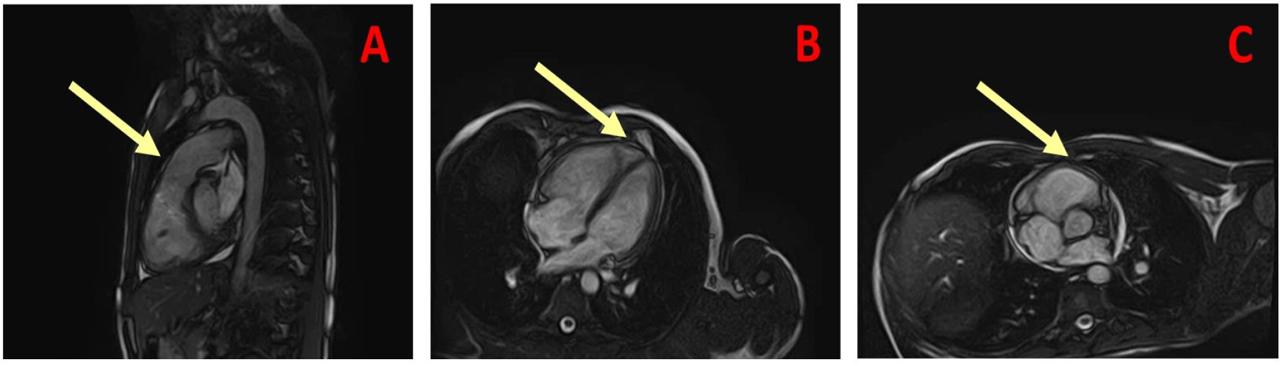

Cardiac magnetic resonance imaging was performed in order to provide additional information on the possible pathophysiological mechanism of cardiac injury. Panel A. MRI confirmed right heart dysfunction, with a RVEF of 31%; Panel B and C. There was no evidence of edema or lipomatous changes on T1 and T2 sequences. Late gadolinium enhancement was confined only to the septal insertion of right ventricular free wall.